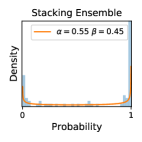

To model how different classifiers will respond to a given input , we assume that the prediction from classifier is sampled from a beta distribution that is characterized by two parameters by and . We further assume that is fixed to the same constant value for all ’s. Under this assumption, each input can be described by ( can be calculated since is fixed), easing further analysis. The Severity Level (SL) of the case represented by image can be characterized by the parameter . The larger the value of , the more severe the case of is. When and are close, the case is ambiguous as the distribution shifts towards being symmetric (i.e. signifying much disagreement among classifiers) rather than being one-sided (i.e. consensus among classifiers that is negative or positive). We provide a set of examples in Figure 2 and also Figure S.8 in the supplementary materials showing how the beta distribution can be used to capture diverse predictions given by an ensemble learner.

Comparing the three ensemble methods in Figure 4, the stacking ensemble method has the highest ratios of SL1 & SL2 data among the high-uncertainty examples it identified under both mean and var. TTA showed slightly better performance than MC-dropout but still falls behind the stacking ensemble method. Considering the fact that SL0 examples accounted for the majority of the dataset, the stacking ensemble method was much more precise (specific) in selecting truly ambiguous data points that were difficult to classify. From Figure 3, we can also see that the stacking ensemble method greatly outperformed the other two methods in finding false negatives under both mean and var uncertainty metrics.

In contrast, the MC-dropout method showed the worst overall performance among the three, as it can be seen from the high ratios of SL0 examples among the uncertain negatives in Figure 4. The histograms in Figure 2 provides another perspective to look into the phenomenon, where a decent proportion of MC-dropout model’s predictions on SL0 inputs entailed low confidence (far from 0 or 1), which from another angle explained why MC-dropout was less specific in terms of lower FNP; many no-DR inputs (i.e. SL0) were erroneously assigned high uncertainty by MC-dropout models.

It is still an open question why the evaluated MC-dropout networks signaled relatively high uncertainty on SL0 & SL3 & SL4 data that are less likely to be ambiguous. We conjecture that much of the “uncertainty” indicated by disagreement among test-time dropout samples actually reflects the stochastic nature of dropout networks rather than the real decision uncertainty associated with the data. It is worth noting that the MC-dropout model we evaluated was not weak per se; they all achieved above Area Under Curve (AUC) scores on test sets. The weakness of individual test-time samples (which explains their low-confidence predictions on SL0 & SL3 & SL4) might have been hidden when they are aggregated into an ensemble—a well-known advantage of ensemble learning. Our results suggested that the uncertainty information given by implicit ensemble methods such as MC-dropout and TTA might not be as reliable as that from explicit ensemble approaches (e.g., stacking ensembles). Similar findings on MC-dropout can be found in some previous papers [1].